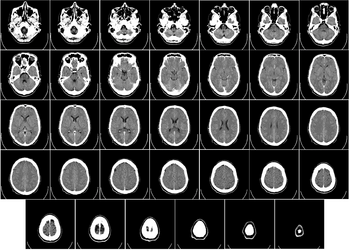

Головной мозг человека занимает почти всю полость мозгового отдела черепа, кости которого защищают головной мозг от внешних механических повреждений. В процессе роста и развития головной мозг принимает форму черепа.

Строение головного мозга

Объём мозга большинства людей находится в пределах 1250—1600 кубических сантиметров и составляет 91—95 % ёмкости черепа. В головном мозге различают пять отделов: продолговатый мозг; задний, включающий в себя мост, мозжечок и эпифиз; средний; промежуточный; и передний мозг, представленный большими полушариями. Наряду с приведённым выше делением на отделы, весь мозг разделяют на три большие части: